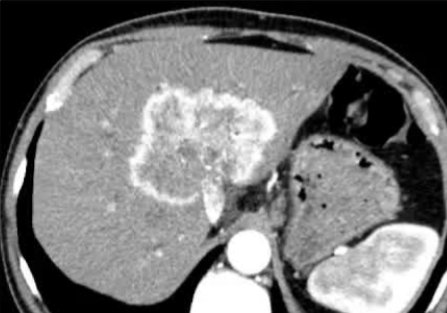

· 单中心、样本量小; 83 岁的女性,体重超标 40 毫米单发 ICC(S7-S8) 中肝静脉和右肝静脉浸润性,活检:非酒精性脂肪性肝炎(慢性肝病),马斯氏(MaS)病(30%)

考虑采用“三步策略 TARE→ PVE → Surgery”方案 剂量活性:1.56 和 3.16 GBq